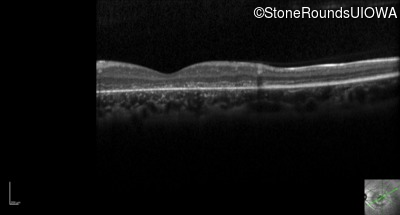

Optical Coherence Tomography - Right - 20/200 -3

Exemplar / OCT Stack

Optical Coherence Tomography - Left - 20/200 -2